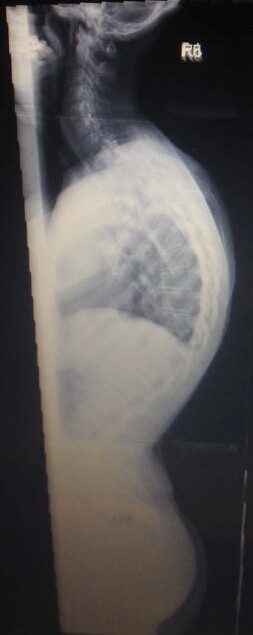

Meine Name ist Claudia bin 30 Jahre und habe eine Hyperkyphose von 80 Grad die im November 2013 endlich festgestellt wurde, eine leichte Skoliose hatte ich schon von Kind an . Am Ende war es so das ich seit über 20 Jahren mit Schmerzen lebe , bis mir vor 4 Jahren wegen unerträglichen Schmerzen eine Bandscheiben OP gemacht wurde da es angeblich davon kam!!! ( nur leider lagen diese ganzen Ärzte bei ( ca.20 Ärzte von Orthopäden, Neurologen und so weiter ) denen ich im lauf der 20 jahre war alle falsch , alle meinten das wären die Bandscheiben

Im Anhang 2 Bilder von mir